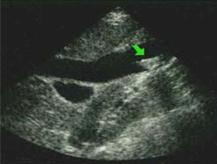

(二)B型超聲顯像具有直視、追蹤及動態觀察等優點。如膽道梗阻而擴張時, 能正確地查出液性內容的所在和範圍,膽管擴張的程度和長度 ,其診斷正確率可達94%以上。應作為常規檢查的診斷方法。